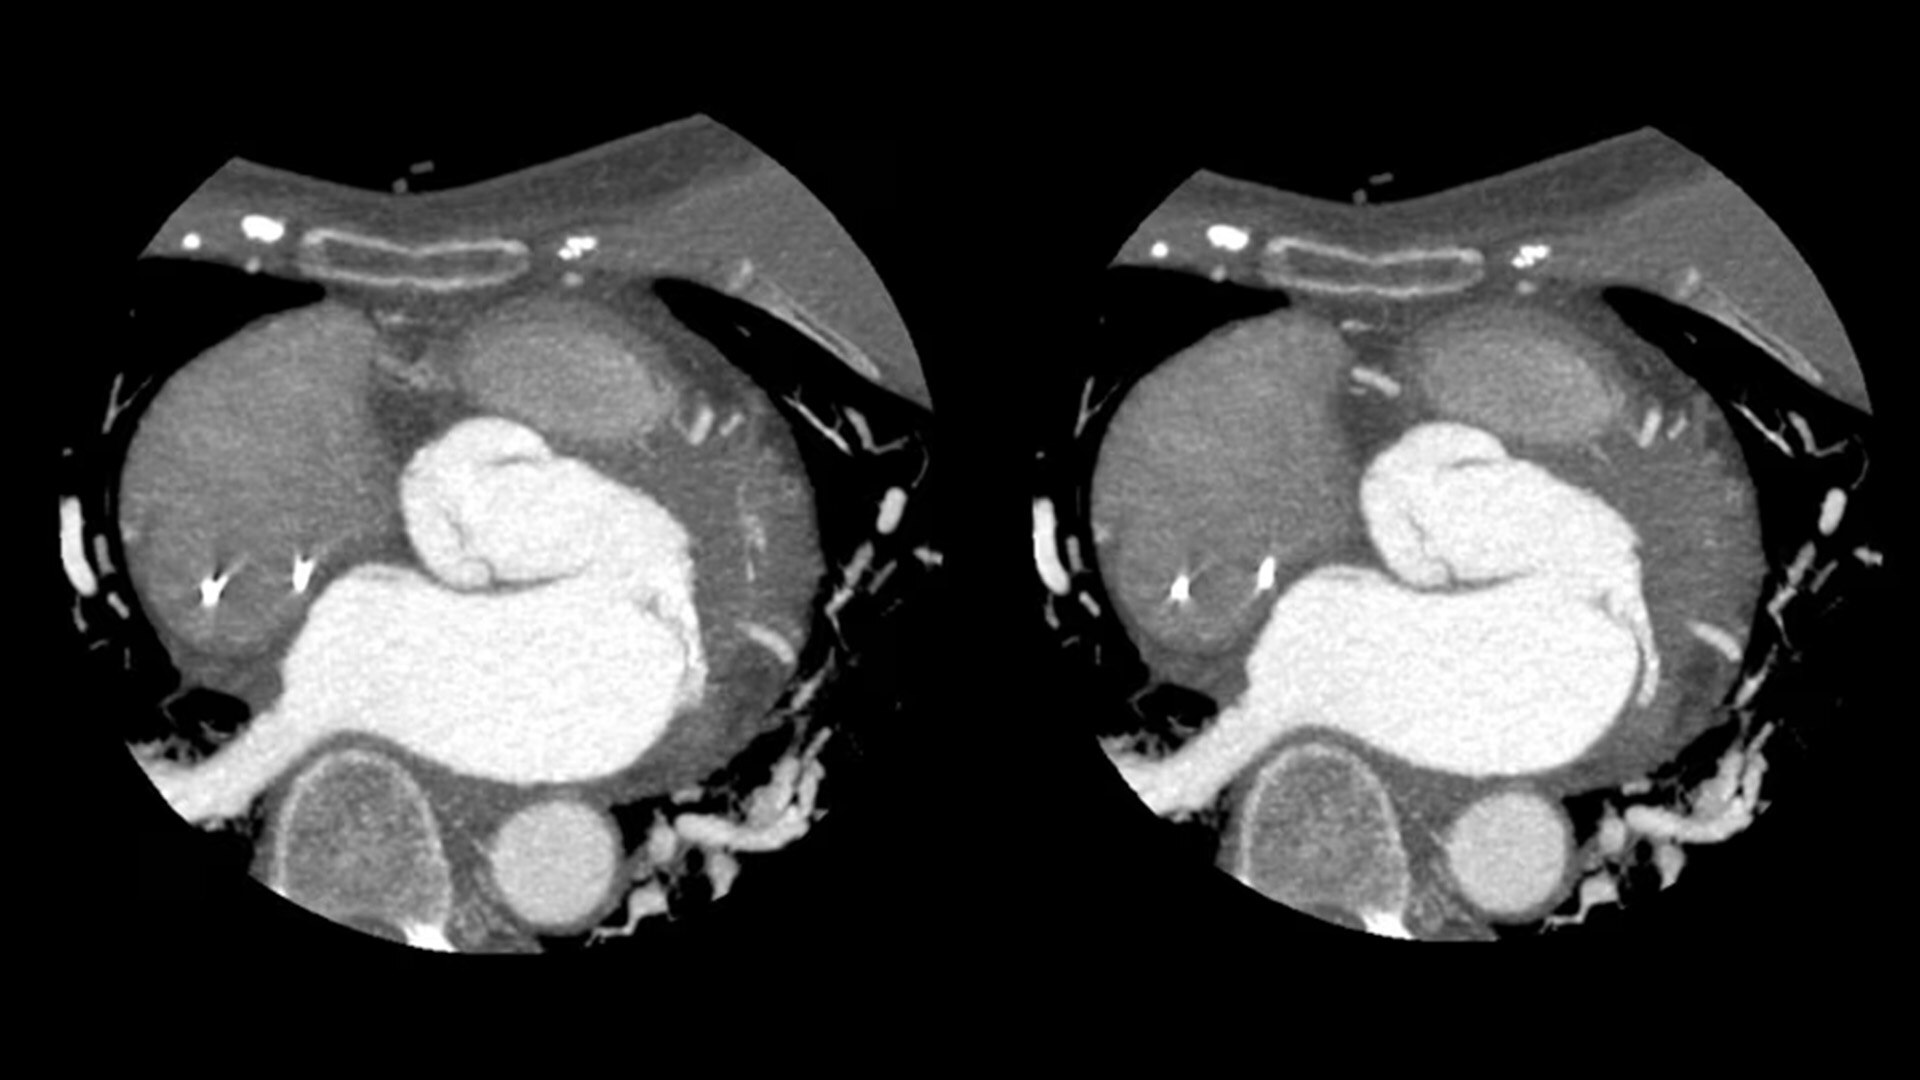

SnapShot Freeze 2

Intelligent and automated whole-heart motion correction for enhanced Cardiac CT imaging.

Motion correction

6x reduction in motion artifacts1